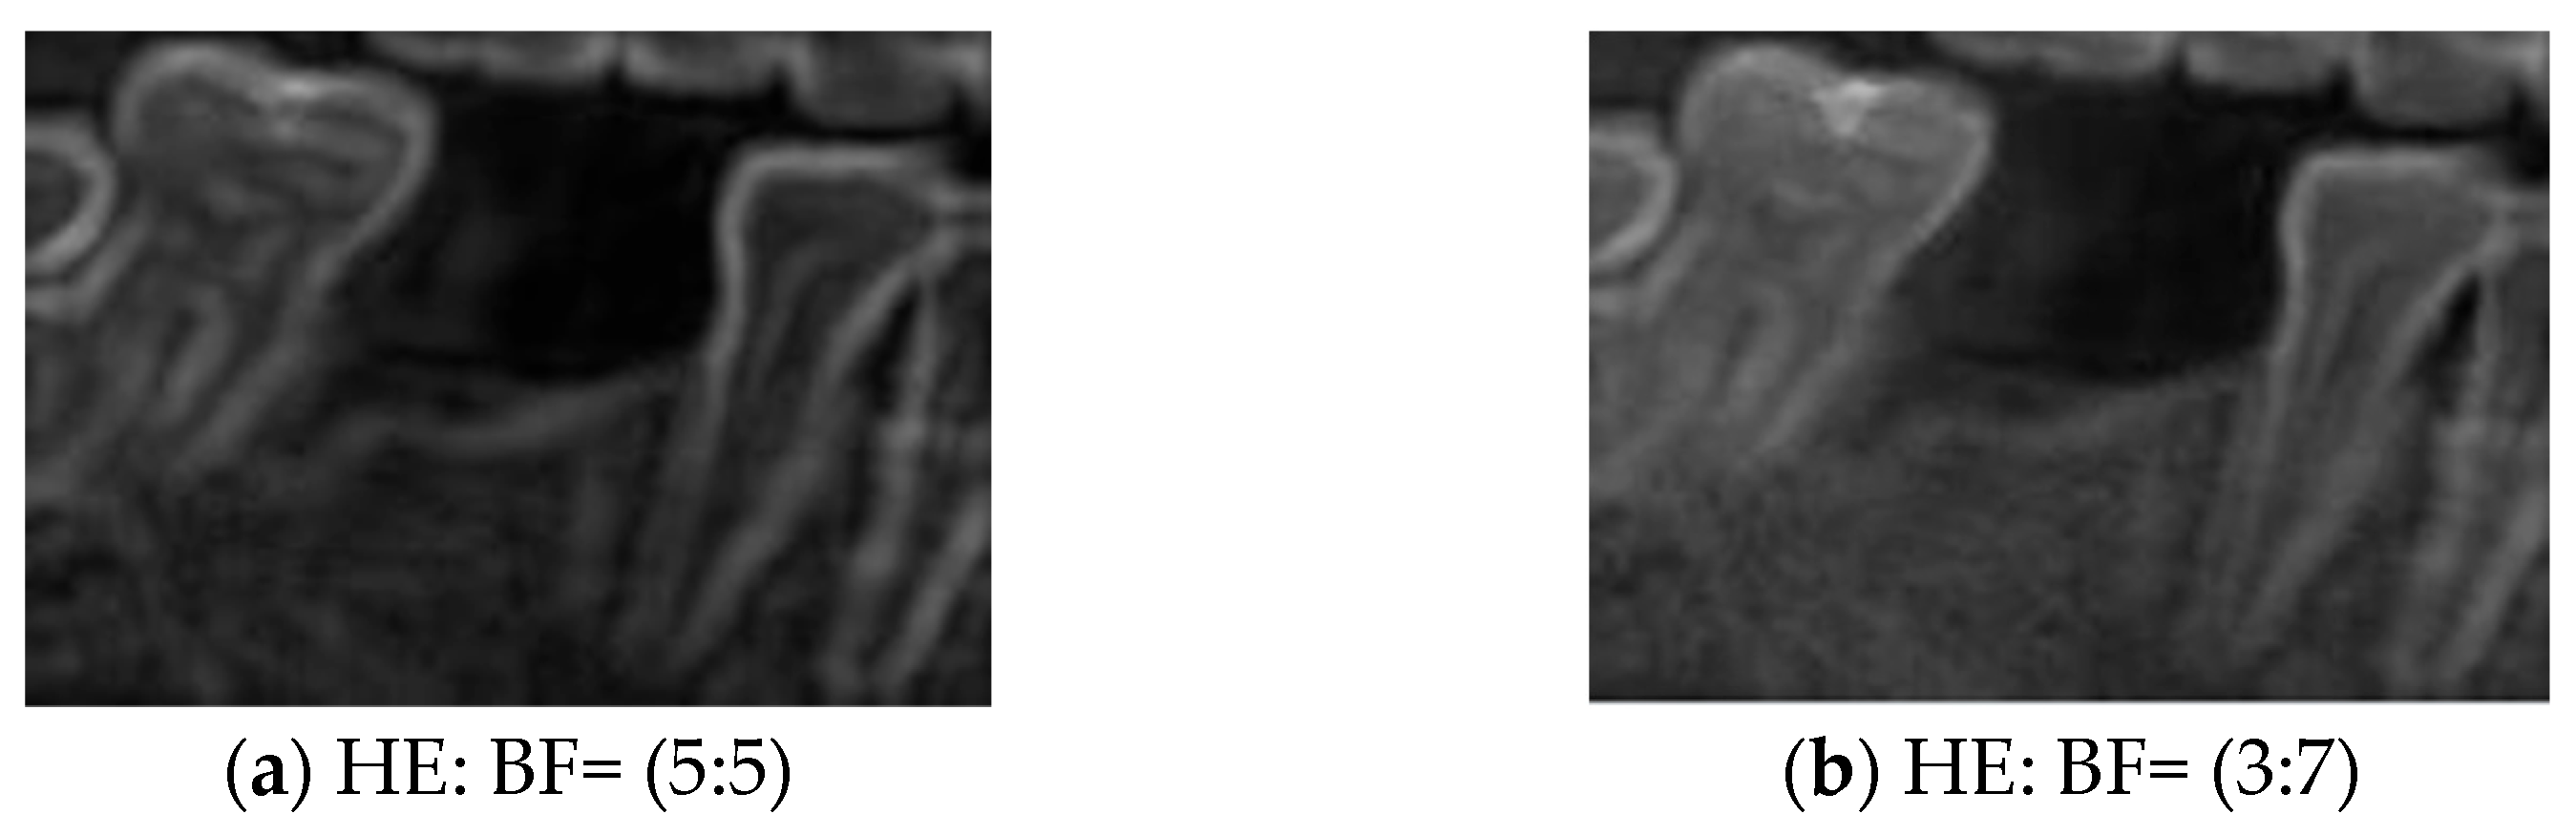

2.3. Tooth Image Enhancement

2.3.1. Bilateral Filter

2.3.2. Histogram Equalization

| HE | 84.77% | 85.79% | 84.98% | 84.50% | 74.60% |

| HE: BF (5:5) | 85.78% | 85.80% | 85.98% | 85.50% | 75.42% |

| HE: BF (3:7) | 89.80% | 89.82% | 89.98% | 89.50% | 78.75% |